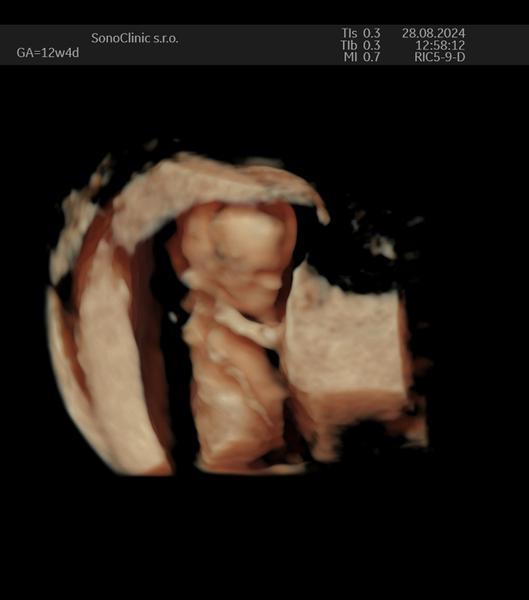

máte niektorá fotky z 3D/4D ultrazvuku? Čakáme s priateľom prvé bábo som momentálne v 12tt a strašne by som naň chcela ísť, ale lekár povedal, že je to ešte zbytočné takto skoro..

Jemine to v 12/13tt vyzera hrozne tie deticky este, ako mimozemstan by som povedala. Na tych beznych usg to vyzera dobre vacsinou, ale to 3D to bol hrozny pohlad, my sme sa na tom dost bavili. Okolo 23 tt, co mas morfo sono velke, tam to 3D je nadhera. To uz je take pekne vyklubane babo. Z toho mame aj videa a strasne pekne to vyzeralo. Hlavne maly sa uz podobal Komplet na seba. V tom 12/13 tt neni dost hmoty mna tom dietatku, to ma este malinku vahu.

@kiki68 Noo akurát pozerám, že v tom 12-13tt to vyzerá ako taký ufonik ešte, tak radšej ešte počkáme aj keď sme veľmi zvedaví už 😅